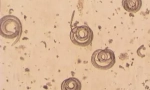

Poslední kategorie zahrnuje chyby, které se mohou objevit v každém domě, rychle násobit a krmí na lidskou krev. Abychom se ujistili, že domácnosti jsou napadeny chybami, je nutné vědět, jak jejich bity vypadají na těle.

Slepý kousnutí na pleť vypadají jako zaoblené červené skvrny s bodem (místo punkce) v centru. Jsou seskupeny několika kusy umístěnými ve vzdálenosti 2-3 cm od sebe. Průměr skvrn může být odlišný, v závislosti na tom, jak moc reakce osoby na mechanické poškození kůže a slinám parazitů. Většina lidí má trochu kousnutí, v některých případech je pozorováno silné těsnění.

Nejčastěji stopy kousků kousnutí jsou umístěny řetězy nebo ostrovy. To je způsobeno tím, že dospělý hmyz dělá několik punkcí, dokud se nestane.